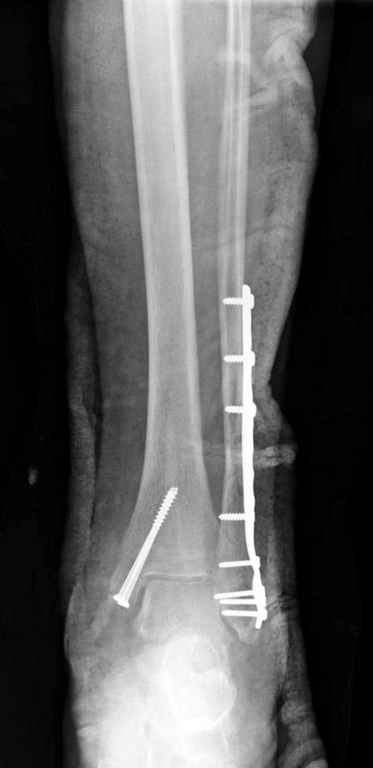

Ув. коллеги.

После проведенной дискуссии пришел к выводу, что трансартикулярная диафиксация не совсем приемлима с учетом современных методик остеосинтеза. Кроме того, вычитал, что хрящ разрушается на расстоянии до 0,5 см от места проведения спицы.

Пока я был в интернатуре, предпочитали осуществлять стабильный остеосинтез с ранней функцией. См. приложения и полнотекстный вариант

статьи.